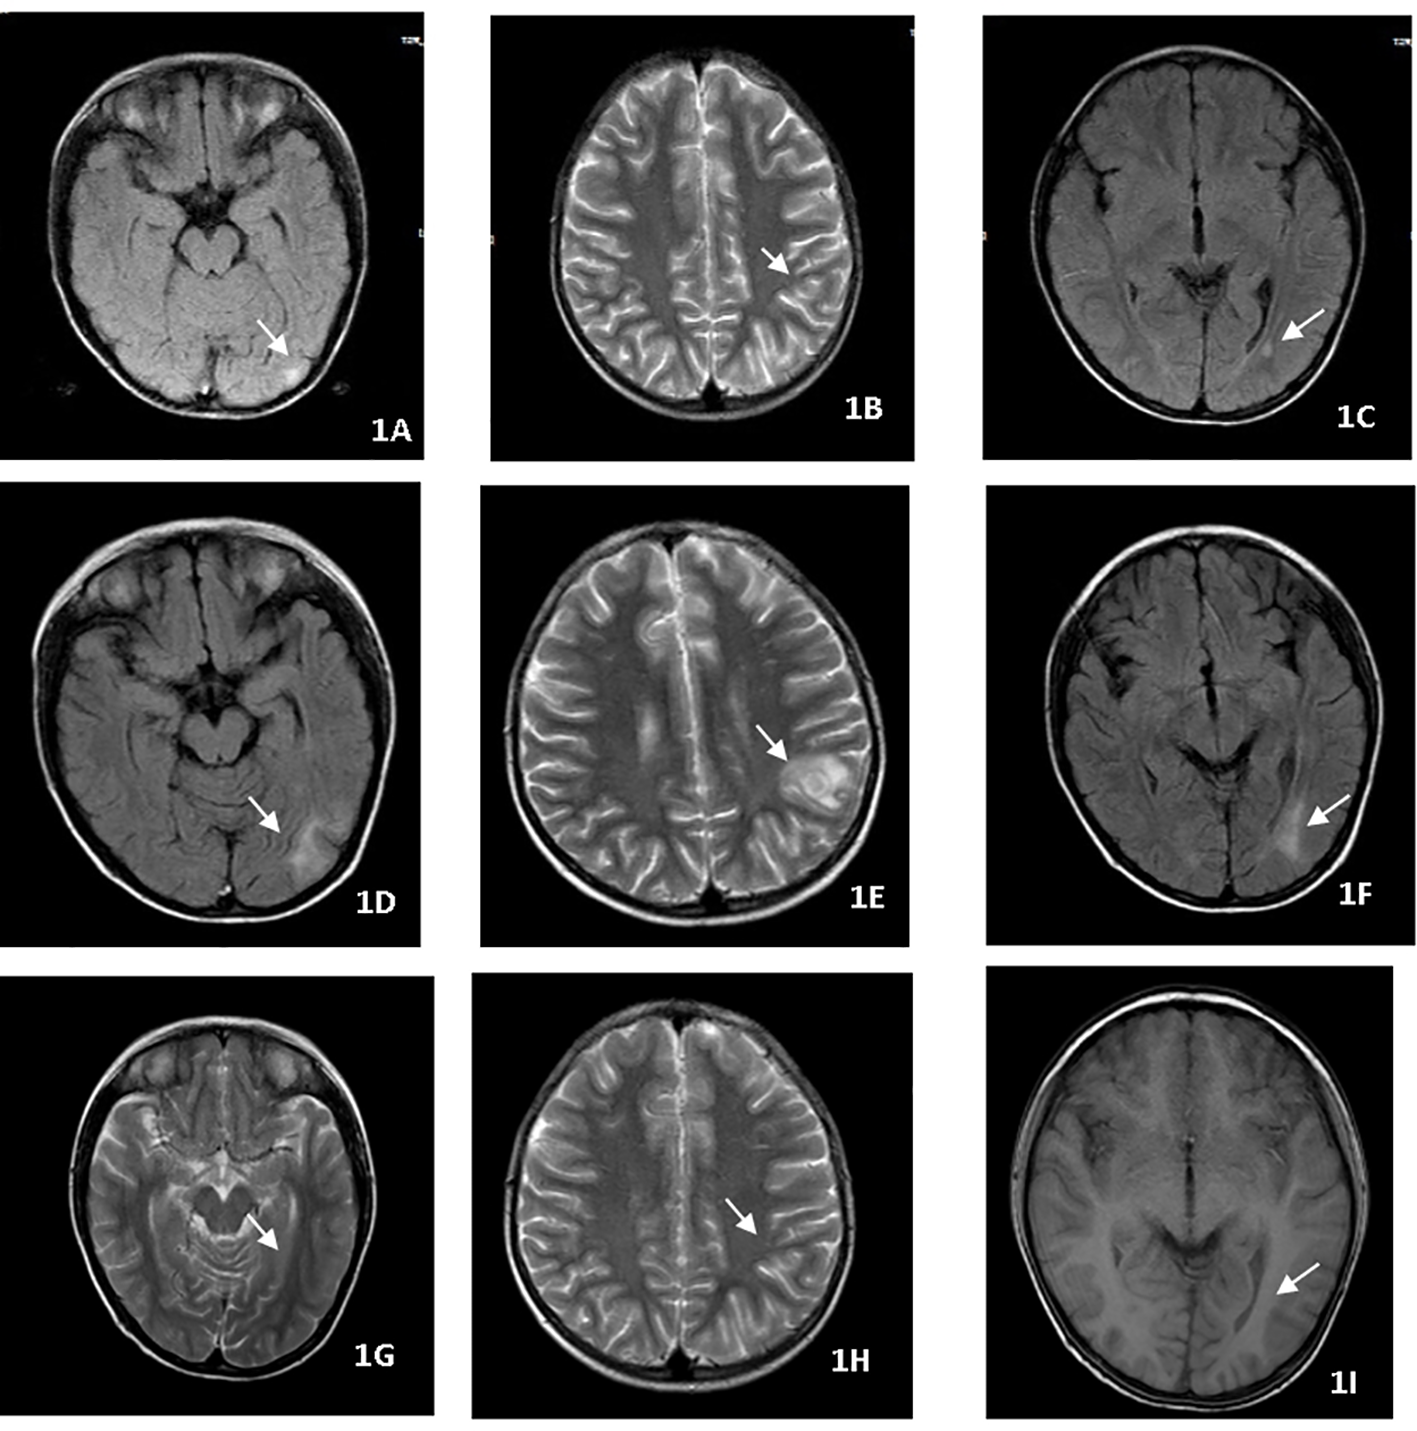

A nine-year-old boy presented with fever, headache, vomiting, and cough. No focal neurology was identified. An MRI (Figures 1A–C) revealed multiple rounded lesions in the left occipital lobe with peripheral enhancement. The proximal end of the right middle cerebral artery was thin, and tuberculous vasculitis was considered. GJ was positive for X-pert MTB/RIF assay and MTB culture with no drug resistance. The patient was started on ATT and dexamethasone for four weeks. Although gradual improvement was observed initially, the patient complained of headache, vomiting, and fever following the reduction of glucocorticoids. Repeat MRI (Figures 1D–F) showed that the left occipital lobe lesion was significantly larger than the anterior lesion. As GJ MTB culture with drug susceptibility testing had been obtained, the possibility of drug-resistant TB was not considered, which made the diagnosis of paradoxical reactions more likely. Therefore, the glucocorticoid dose was maintained and thalidomide was initiated at a dose of 4 mg/kg/d for two months,Thalidomide treatment improved the intracranial lesions (Figures 1G–I). ATT was maintained for one year. The patient has since recovered.

Figure 1

(A–C) MRI revealed multiple rounded lesions in the left occipital lobe with peripheral enhancement. (D–F) MRI showed that the left occipital lobe lesion was significantly larger than the anterior lesion. (G–I) Thalidomide treatment improved the intracranial lesions after 2 months.